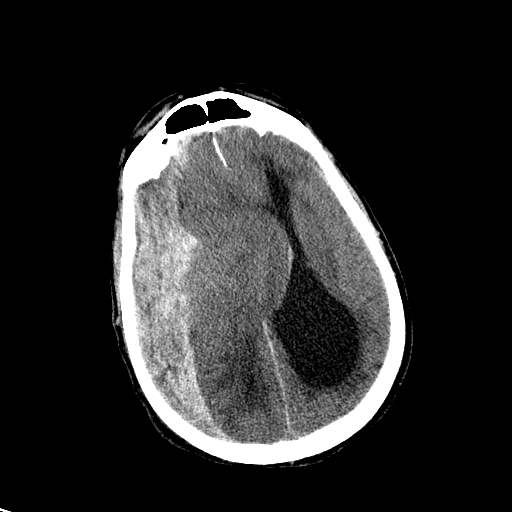

- Outcome Prognostication in Traumatic Brain Injury (OPTIMISM) Study

Outcome Prognostication in Traumatic Brain Injury (OPTIMISM) Study

Objectives: To study the short and long-term outcomes after moderate to severe traumatic brain injury (msTBI) that may lead to new and improved TBI treatment.